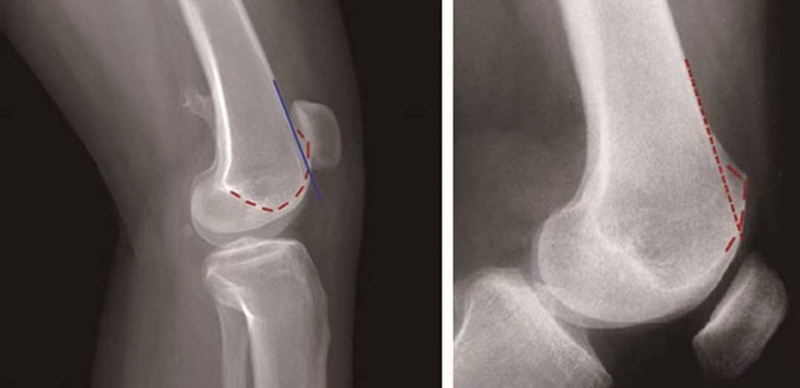

①交叉征:

H.Dejour在1987年介绍了股骨滑车发育不良在膝关节标准侧位X线片的特殊表现,描述了交叉征(crossing sign)。在股骨滑车发育不良的膝关节标准侧位像上,股骨滑车沟基底线会与股骨外髁的轮廓线相交叉,即为交叉征(图11),意味着股骨滑车发育平坦。

图11 交叉征

②突起征:

H.Dejour在1996年提出突起征(spur或bump)或滑车近端突起征(supratrochlear spur),是指在膝关节标准侧位像上,股骨滑车沟基底线的最高点位于股骨前方皮质延长线的前方(图12)。这种征象的实质是股骨滑车近端的整体抬高。在膝关节屈曲早期,髌骨必须越过滑车近端的突起才能进入股骨滑车,因此,容易出现髌骨向外脱位。如果突起征>5mm即为异常,意味着股骨滑车基底高于股骨外髁的轮廓。

图12 突起征

③双轨征(或称为双线征):

是指在膝关节标准侧位像上,代表股骨内外侧滑车的两条线分开,呈双轨样(图13)。它的出现提示股骨内侧滑车发育低平,导致它的前缘出现晚于外侧滑车。

图13 双轨征

(3)股骨滑车发育不良的分型:

1996年,D.Dejour和B.Le Coultre提出了更准确的股骨滑车发育不良的四种分型(图14):

图14 股骨滑车发育异常分型 A型:交叉征;B型:交叉征+突起征;C型:交叉征+双线征;D型:交叉征+突起征+双线征